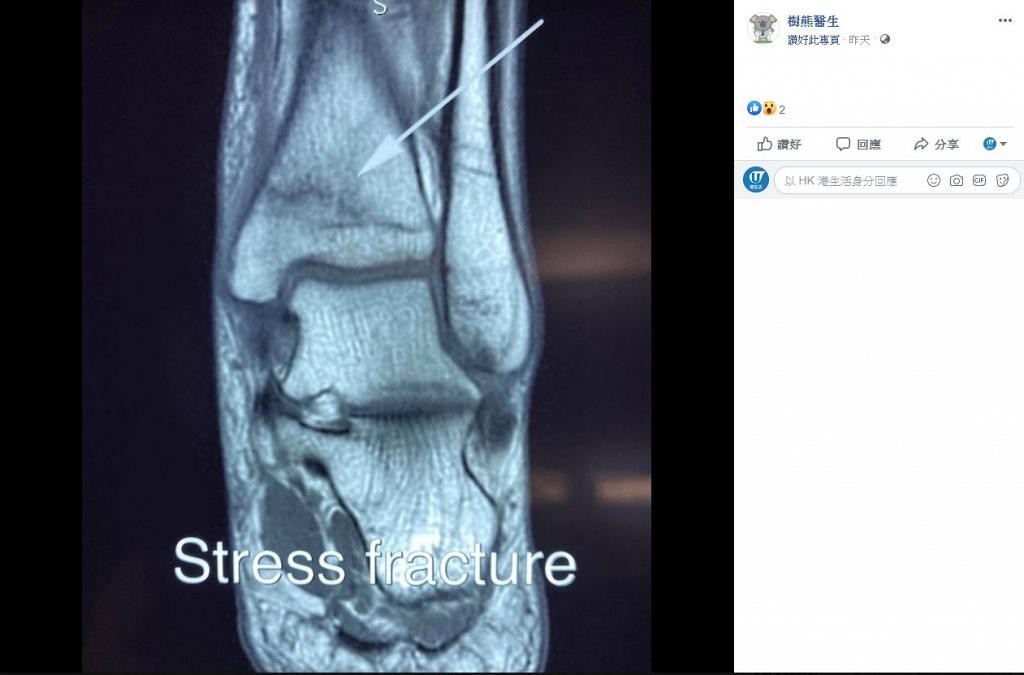

近日,醫善同行慈善基金的Facebook專頁「樹熊醫生」就分享了一單骨科醫生的真實個案,提到有一名40歲的病人求診,指自己突然出現原因不明的腳痛情況。據醫生診斷後,得出結果為「壓力性骨折」,而原因竟然是港人熱愛的遊戲Ring Fit!

原來這名病人每天都有赤腳與家人在家玩Ring Fit的習慣,每次時間更長達1至2小時,期間不時有原地跑跳的動作出現。直至突然有一天,他的身體出現原因不明的腳痛,走路的時間越長,疼痛的情況就越嚴重。據該名病人透露,他過往並無任何受傷的病史,x-光及血液檢查結果亦無大礙,在醫生再三追問後,才得知原來他這個每天與家人玩Ring Fit的習慣,極有可能就是骨折的主要成因。

壓力性骨折,又稱為疲勞性骨折,常見於長跑選手、籃球員、芭蕾舞蹈員及軍人等職業,當外來壓力超出了骨骼本身可承受的力量,就會發病。按理來說,普通人較少會遇到這個病症,可是當平常沒有運動習慣的人,突然提升運動量便有機會惹上壓力性骨折。受傷的部位在活動時感到疼痛是常見的病徵,只要有關部位不再受力或負重時,痛楚便會減輕。

壓力性骨折的治療方法與一般性骨折相似,若使用非手術治療,配戴矯形器或以石膏定位,就能幫助骨骼自癒,同時可輔以止痛劑和物理治療來減輕痛楚,康復時間約3個月。